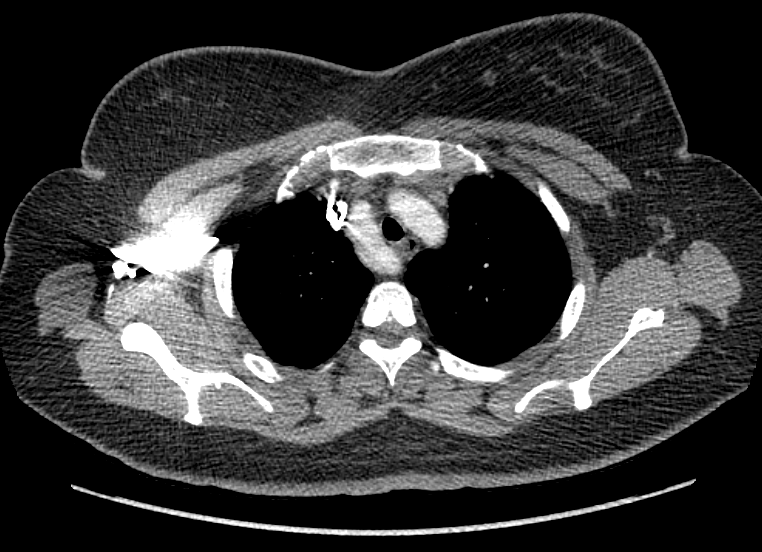

F/34

°Ç°­°ËÁø»ó ½ÃÇàÇÑ Chest PA »ó mediastinal widening ¼Ò°ßÀ¸·Î further evaluation À§ÇØ ³»¿øÇÔ.

Áõ»óÈ£¼Ò ¾øÀ¸¸ç ½Åü°ËÁø»ó ƯÀÌ¼Ò°ß ¾øÀ½.